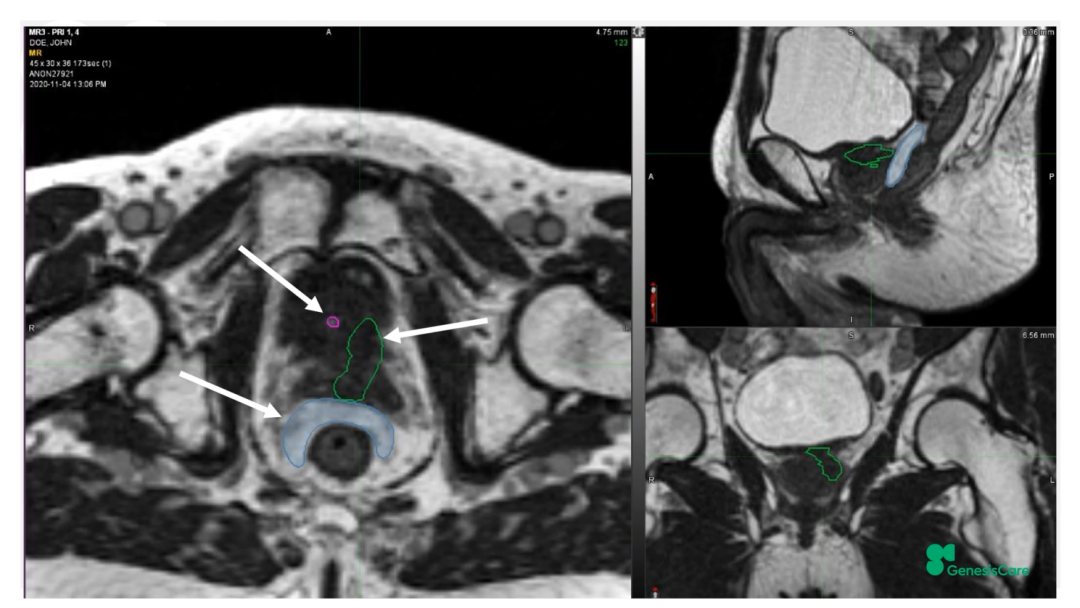

Dr. CamilleriÏÈÈÝÁËһλ72Ë꣬£¬£¬£¬£¬£¬£¬ÔÚ2006Äê½ÓÊÜÁË55Gy/20F·ÅÁƺ󸴷¢µÄǰÏßÏÙ°©»¼Õß¡£¡£¡£¡£¡£¡£ÆäʱËüµÄPSAΪ28£¬£¬£¬£¬£¬£¬£¬¾Ö²¿ÍíÆÚ£¬£¬£¬£¬£¬£¬£¬ÆÚ±ðΪT3aN0M0¡£¡£¡£¡£¡£¡£PET-CTÏÔʾǰÏßÏÙ×óºó²¿¾Ö²¿¸ß´úл£¬£¬£¬£¬£¬£¬£¬»î¼ìҲ֤ʵÁËÕâÒ»µã£¬£¬£¬£¬£¬£¬£¬²¢ÇÒ»î¼ìЧ¹ûÅú×¢Ö×ÁöÇÖÈë×ó²à¾«ÄÒÏٵײ¿¡£¡£¡£¡£¡£¡£½«ÆäMRIdian MRIͼÏñºÍPET-CTͼÏñÈںϺ󣬣¬£¬£¬£¬£¬£¬ÔÙÆ¾Ö¤»î¼ìЧ¹ûÈ·¶¨°ÐÇø£¬£¬£¬£¬£¬£¬£¬¼ûFigure 20-22£¬£¬£¬£¬£¬£¬£¬²¢ÖÆ×÷·ÅÁÆÍýÏë¡£¡£¡£¡£¡£¡£·ÅÁƼÁÁ¿Îª35Gy/5´Î£¬£¬£¬£¬£¬£¬£¬Äý½º×è¸ôÎïºÜºÃµØ°üÀ¨ÁËÖ±³¦£¬£¬£¬£¬£¬£¬£¬¼ûFigure 23£¬£¬£¬£¬£¬£¬£¬°ÐÇøºÍΣ¼°Æ÷¹ÙÊÜÁ¿¼ûFigure 24¡£¡£¡£¡£¡£¡£»£»£»£»£»£»£»¼ÕßÓÚ2020Äê12Ô½ÓÊÜÖÎÁÆ£¬£¬£¬£¬£¬£¬£¬ËûÌåÖʺܺ㬣¬£¬£¬£¬£¬£¬ÔÚ·ÅÁÆÊ±´úºÍÖ®ºó£¬£¬£¬£¬£¬£¬£¬¼á³ÖÿÖÜÈý´Î5¹«ÀïÅܲ½£¬£¬£¬£¬£¬£¬£¬Ê¼ÖÕδ·ºÆðGUºÍGI¶¾ÐÔ¡£¡£¡£¡£¡£¡£ËûµÄPSA×îµÍֵΪ0.45£¬£¬£¬£¬£¬£¬£¬ÔÚ2022Äê5ÔµÄËæ·ÃÊý¾ÝÖУ¬£¬£¬£¬£¬£¬£¬ØºÍè¼¤ËØË®Æ½»Øµ½ÁËÕý³£µÄ33%¡£¡£¡£¡£¡£¡£ÔÚ2022Äê1ÔµķÅÁƺóPSMA PETµÄͼÏñÉÏ£¬£¬£¬£¬£¬£¬£¬Î´¼ûÖ×Áö¸ß´úл¼ûFigure 25¡£¡£¡£¡£¡£¡£